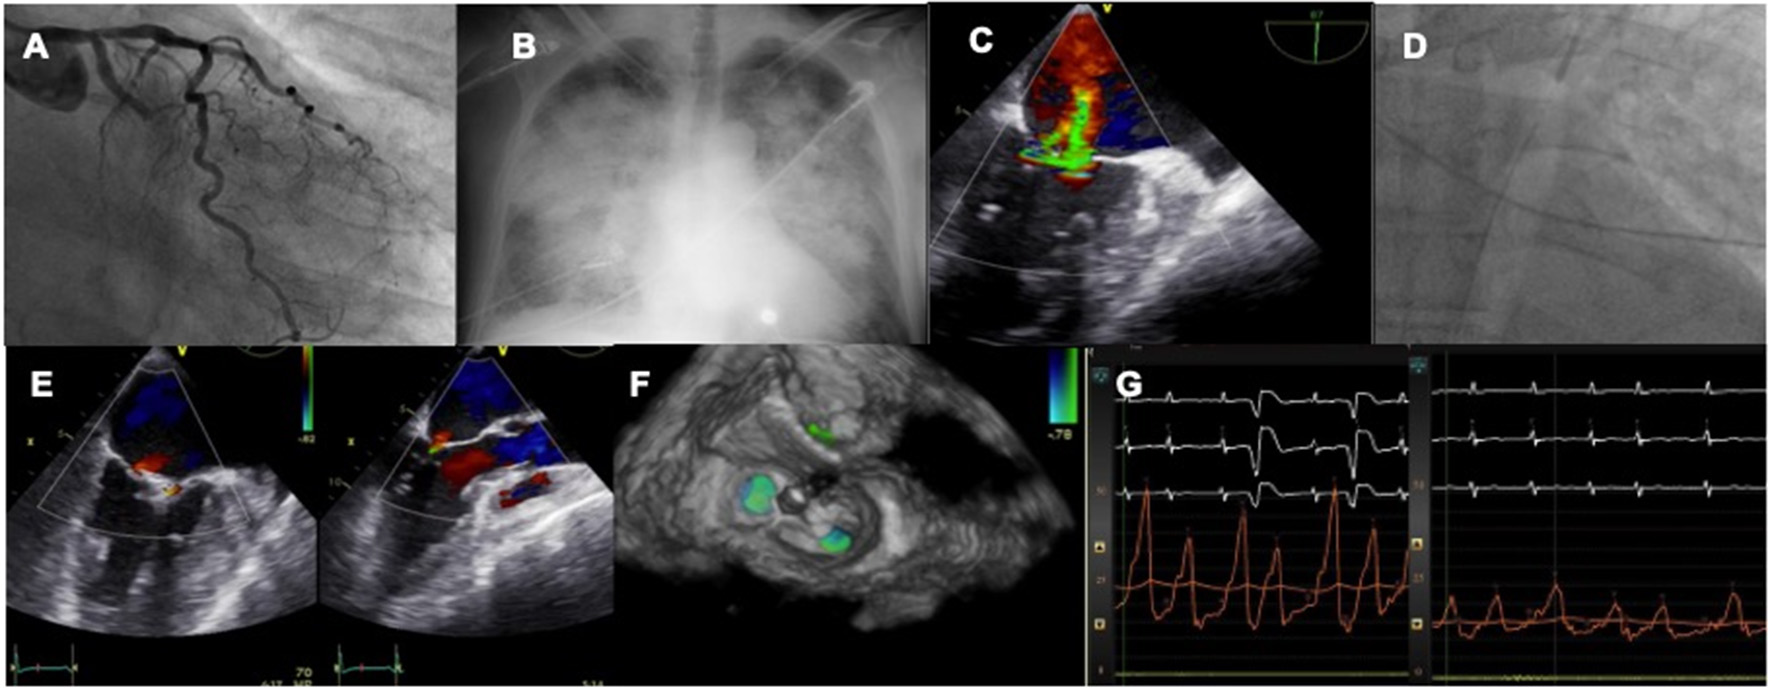

The first experiences with MitraClip were case reports and small series of cases showing the feasibility of treating this complex scenario with a percutaneous device in both cases of subvalvular apparatus rupture or those more functional (39–44). In that series of extreme risk patients TEER was associated with significant clinical and hemodynamic improvement, setting the field for larger registries to come (Figure 2).

Figure 2

Case of acute MR after MI treated by TEER. A patient with LCX myocardial infarction (A) develops rapid pulmonary edema (B) and severe MR is diagnosed with echo (C). An IABP is inserted to stabilize the clinical condition (D). The valve is repaired with two MitraClip (E,F) leading to an acute drop in left atrial pressures (G).